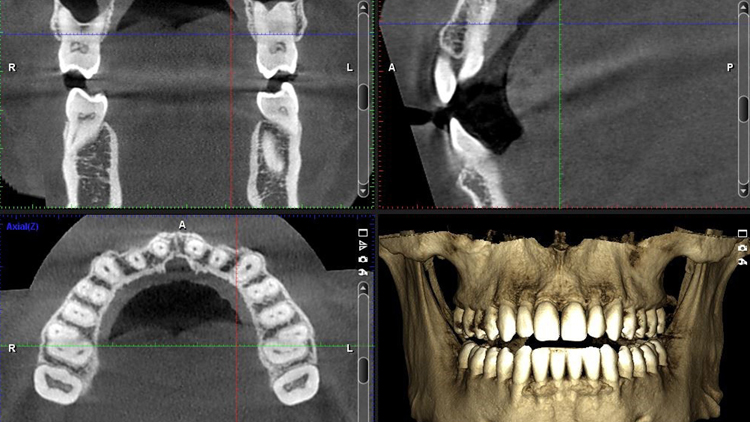

What is 3D Tomography?

3D tomography is one of the most advanced imaging methods used in dentistry. Unlike traditional X-rays, it provides a three-dimensional view of the teeth, jaw, and facial structure. This allows even the finest details to be seen, ensuring highly accurate treatment planning. It offers significant advantages, particularly in implant surgery, jaw joint disorders, and the positioning of impacted teeth.

When is 3D Tomography Used?

In implant treatment planning → Measures the thickness and height of the jawbone.

In diagnosing gum and periodontal diseases → Provides a detailed view of bone loss.

In detecting cysts, tumors, or infections → One of the most reliable methods for early diagnosis.

In orthodontic planning → Assesses the position and symmetry of teeth within the jaw.

In oral and maxillofacial surgery → Evaluates impacted wisdom teeth and jaw joint disorders.

Treatment Planning After 3D Tomography

With the obtained images, the dentist can design a personalized treatment plan for the patient:

Implant placement and angulation are determined with precision.

If necessary, the need for a bone graft is identified in advance.

In cases of jaw joint disorders, the most suitable surgical approach is selected.

In conclusion, 3D tomography makes the treatment process both safer and more predictable.